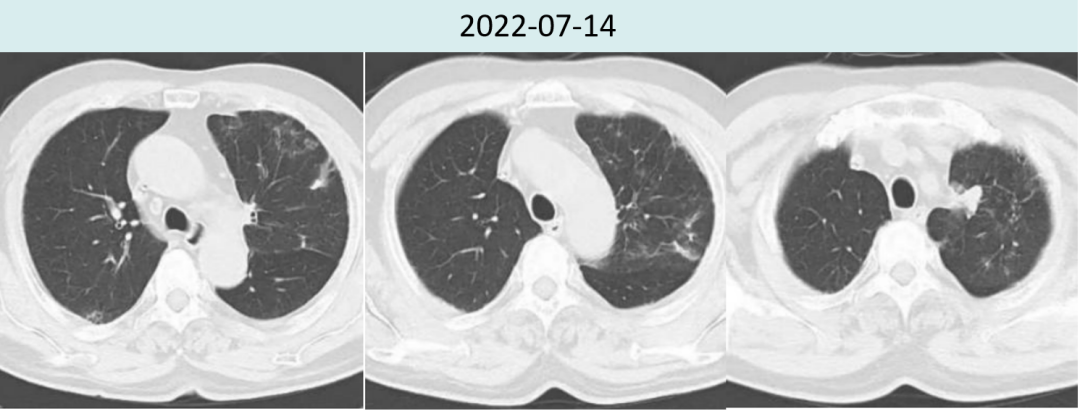

2021年6月18日治疗两周期后复查胸部CT提示:肿瘤较前明显缩小(4.5cm→2.0cm),新增多发炎性病灶,总体疗效评价为PR。

图1.患者治疗前后胸部病灶对比

2021年8月11日激素治疗6周后,胸部CT提示两肺炎症较前进?步好转。肿瘤疗效评价持续PR(4.5cm→1.6cm)。

2021年8月11日免疫性肺炎已缓解至≤G1级。

2022年7月14日斯鲁利单抗联合安罗替尼治疗两周期后,胸部CT提示肿瘤病灶较前再次缩小,疗效评价PR(2.9cm→1.6cm),且两肺间质性炎症较前好转。

图3.患者治疗前后胸部病灶及肺炎情况对比